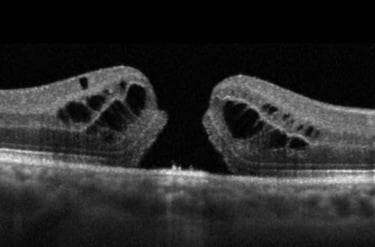

3. Cystoid Macular Edema (CME)

Cystoid macular edema (CME) is a condition in which fluid accumulates in the macula, causing swelling and blurred central vision. CME is often a complication of other retinal conditions like diabetic retinopathy, macular degeneration, or after eye surgery such as cataract surgery. Symptoms include:

Blurry or fluctuating central vision

Distorted or wavy lines

Sensitivity to light

CME can often be managed with medications such as steroids or anti-VEGF injections, which reduce swelling and improve vision. If the condition persists, additional treatments or surgery may be required.

Optical Coherence Tomography (OCT): This non-invasive imaging test provides detailed cross-sectional images of the retina to detect swelling, fluid, or retinal tears.